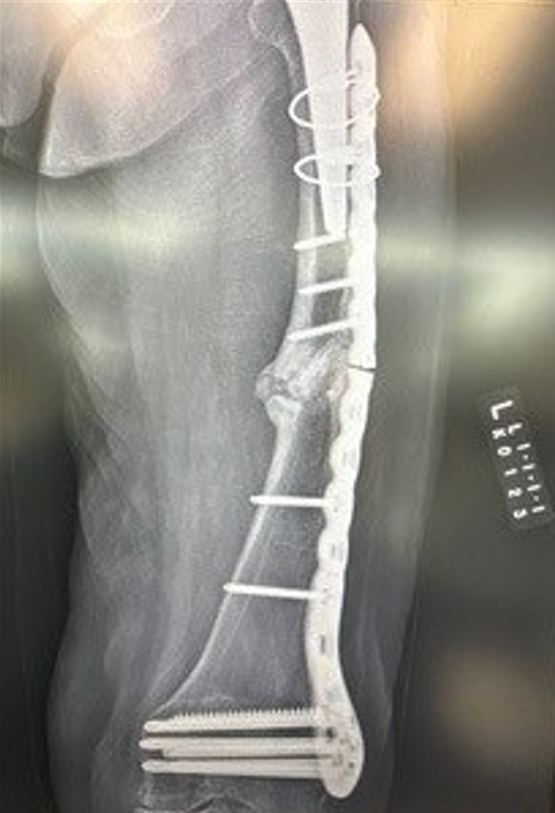

IlluminOss allows you to put screws where you want them, giving you stability, strength, and flexibility in your difficult cases. 🦴 #IlluminOss #Spreadthelight #Orthopedics

Pelvis is an approved indication in the US. For more detailed procedural information including Indications, Warnings, Cautions, Risks & Contraindications, visit illuminoss.com.